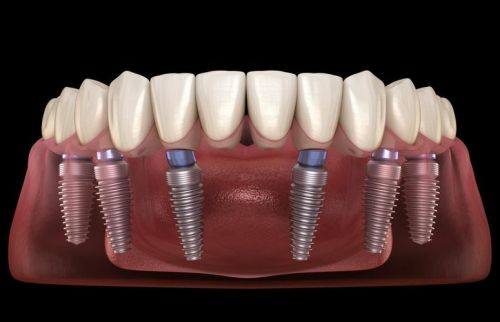

1. 种植牙:种植牙是西安弗莱堡口腔的特色与主打项目。医院设备齐全,拥有精良的数字化种植技术,能够借助完善的数字化设备精细测量患者口腔结构和骨骼情况,通过三维影像技术精细定位种植体位置,为种植方案设计提供详细的数据支持。同时,使用数字化导板确保种植体在手术中精细植入,减少手术时间,提高手术成功概率。此外,西安弗莱堡口腔还开展了all-on-4全口/半口即刻负重种植、穿颧穿翼疑难种植以及高龄种植技术等特色项目。其中,all-on-4全口/半口即刻负重种植可让患者在一次手术中完成多颗牙齿种植,大大节省治疗时间,还能提供更好的咀嚼功能和美观成效,提升患者生活质量。穿颧穿翼疑难种植则是针对牙槽骨萎缩、重度吸收等复杂疑难种植牙病例,西安弗莱堡口腔拥有经验多的医护团队和精良设备技术,能制定个性化治疗方案并取得良好成效。高龄种植技术方面,医院针对高龄患者有丰富的种植经验,医生团队会根据患者身体状况和口腔情况制定个性化治疗方案。

西安弗莱堡口腔的收费合理且透明公开,提供多种种植牙方案供患者选择,价格从1580元起,涵盖了不同品牌和技术的种植体。例如,韩国DIO种植牙价格1580元起/颗,韩国登腾种植牙特价2580元起/颗,奥齿泰种植牙优惠价格3490元起/颗,瑞士iti种植牙集采价格5980元起/颗,瑞典诺贝尔种植牙价格5980元起/颗。半口种植牙集采价格2万元起,全口种植牙集采价格4万元起,全口即刻负重种植牙价格10万元起。此外,矫正牙齿价格16800元起,牙齿修复价格268元起 - 1280元起。医院还会不定期推出多种优惠活动,如来院种植牙可获得牙冠等礼品,进一步降低患者的治疗成本。不过需要注意的是,具体价格应以到院后实际消费情况为准。